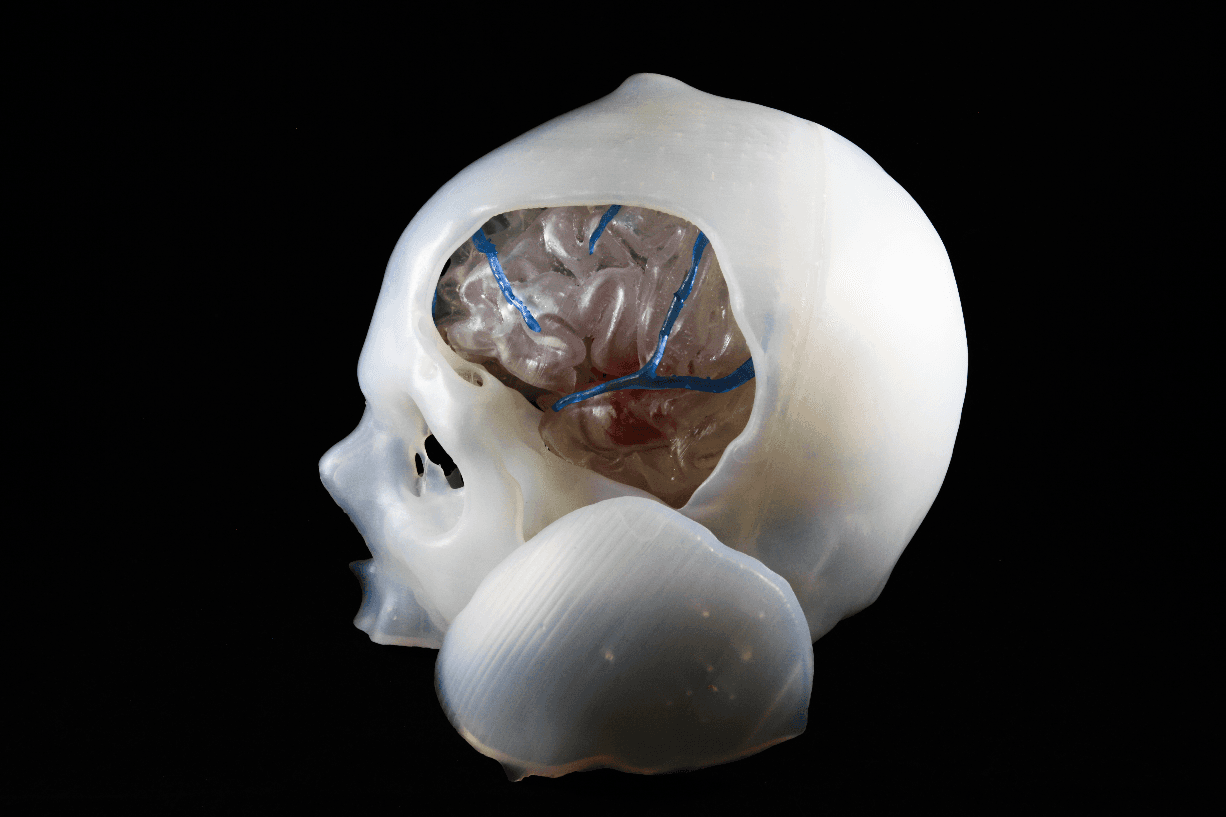

3D-gedruckter Schädel, in dem Gehirn und Arterien sichtbar sind. Der Schädel dient zum Training von Kraniotomien und wurde von TrabTech entwickelt (https://trabtech.co).

Die Technologie der visuellen 3D-Simulation hat in den letzten Jahren beeindruckende Fortschritte verzeichnet. Für viele Operationsteams haben jedoch physisch greifbare Modelle und die Möglichkeit, Eingriffe an einem maßgefertigten Modell üben zu können, einen noch größeren positiven Einfluss auf die Operationsergebnisse. Die mehrschichtigen, segmentierten und vollständig integrierten Modelle von TrabTech können bei Kraniotomien eine Hilfe bieten. Hierbei müssen die Operierenden nämlich in den Schädel bohren und zur Zugangsbildung einen Teil davon ausschneiden – ein Vorgang, der sich Fenestrierung nennt –, ohne dabei das darunterliegende Gewebe zu verletzen.

Das individuelle Modell erlaubt es dem OP-Team nicht nur, die Anatomie zu visualisieren, sondern auch den Eingriff zu simulieren. So erhalten Chirurg*innen die Chance, den operativen Eingriff im Vorhinein zu üben und verschiedene Herangehensweisen an die Behandlung der Pathologie zu testen. Dadurch können sie die Vor- und Nachteile bestimmter Operationstechniken überblicken und Hindernisse erkennen.

3D-gedruckter Schädel, in dem Gehirn und Arterien sichtbar sind, zur Übung von Kraniotomien.

Das Gute an 3D-gedruckten Modellen ist, dass das Gehirn transparent dargestellt werden kann, sodass das Aneurysma und die Gefäße unter dem Temporal- und Frontallappen leicht sichtbar sind. Die Bedeutung physischer 3D-gedruckter Modelle im Vergleich zu digitalen 3D-Modellen wird offensichtlich, wenn das OP-Team nicht über die erforderliche Erfahrung für einen Eingriff verfügt. Hier kann ein 3D-gedrucktes Modell helfen, die Position eines Aneurysmas und die Kraniotomie zu standardisieren.

Zwar lassen auch digitale 3D-Modelle es zu, virtuelle Segmentierungen und Anpassungen wie etwa Positionsänderungen durchzuführen, aber das haptische Feedback fehlt. Mit 3D-gedruckten Modellen erhalten Chirurg*innen verschiedene Blickwinkel auf das Gehirn. Wurde das Modell jedoch einmal beschädigt oder zerschnitten, lässt sich das nicht mehr rückgängig machen.

Materialien, die für den 3D-Druck von Modellen genutzt werden: In diesem 3D-gedruckten Modell wurde die Anatomie der Hirngefäße, des Gewebes und des Schädels durch Scans gewonnen. Die Knochenmodelle wurden aus Durable Resin gedruckt, während für das Gewebe und die Gefäße Elastic 50A Resin verwendet wurde. Die Modelle wurden auf dem Form 3 gedruckt, der inzwischen durch den neueren Form 3B+ ersetzt wurde.

Hanalioglu wählte Elastic 50A Resin wegen seiner elastomerischen Eigenschaften, denn seine Fähigkeit, Arteriengewebe nachzuahmen, ist für ein genaues Verfahren von Vorteil. Wie er berichtet, gab es in den letzten Jahren „Verbesserungen bei den Materialien. Sie fühlen sich viel mehr wie Arterien an. Es gibt immer noch Raum für weitere Verbesserungen, aber die Haptik ist besser.“

Abschließend lässt Hanalioglu sein gedrucktes Arterienmodell lackieren, um die Identifizierung der einzelnen Teile zu erleichtern. Die Möglichkeit, weiche Materialien wie Elastic 50A Resin zu lackieren, ist ein weiterer Vorteil des Materials.